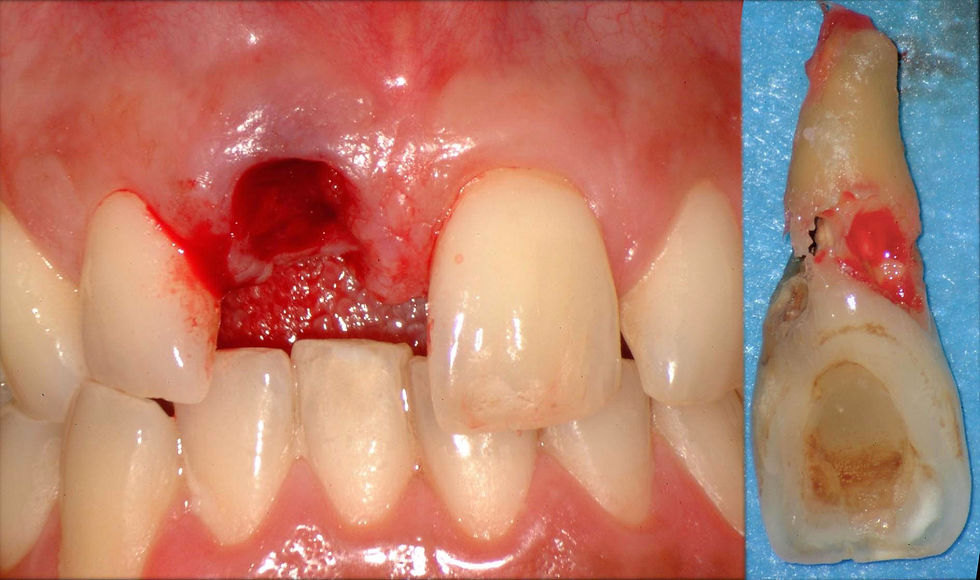

Extraction of the compromised element.